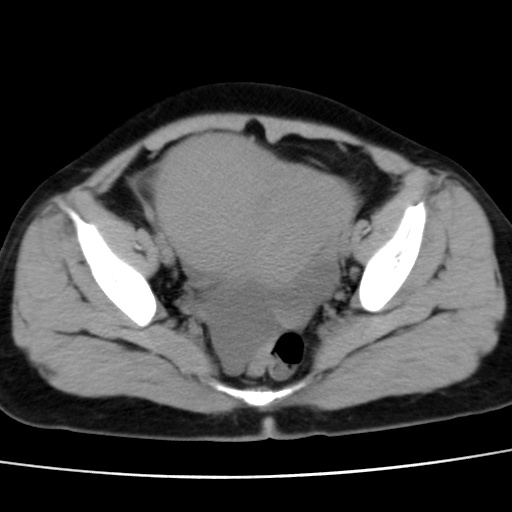

子宫多发肌瘤吗

多发性子宫肌瘤.

考虑多发子宫肌瘤,子宫直肠窝双囊性占位,另直肠周围脂肪密度增高,不知有何病史

支持考虑多发子宫肌瘤~!子宫直肠陷凹积液?

支持考虑多发子宫肌瘤~!子宫直肠陷凹积液!

子宫肌瘤,宫体部后方见液性密度影,是肠道还是子宫与直肠陷窝积液不好说,我觉得它的位置有点高

支持考虑多发子宫肌瘤!子宫直肠陷凹积液!

患者发热,而子宫直肠窝液性灶有明显边缘且局限且囊性,不除外为包裹性积液或脓肿

支持考虑多发子宫肌瘤,子宫直肠陷凹积液可能。

考虑多发子宫肌瘤

1)考虑子宫肌瘤可能性大。2)子宫后方囊性占位性病变,不排除卵巢囊肿可能。

考虑多发子宫肌瘤。子宫后方囊性占位性病变,不排除卵巢囊肿可能。